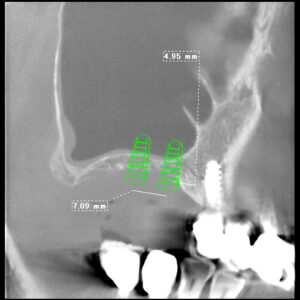

本日はラテラルスリットというサイナスリフトの侵襲を少なくした 我々で考えたオペでした。 サイナスリフトなどのやや難しいといわれるオペは 骨材料の改良や骨と優位に接着するインプラント体の改良 オペ法の改良により 腫れにくく 埋入したいところにインプラントを なるべく短期間に成功させるこ…